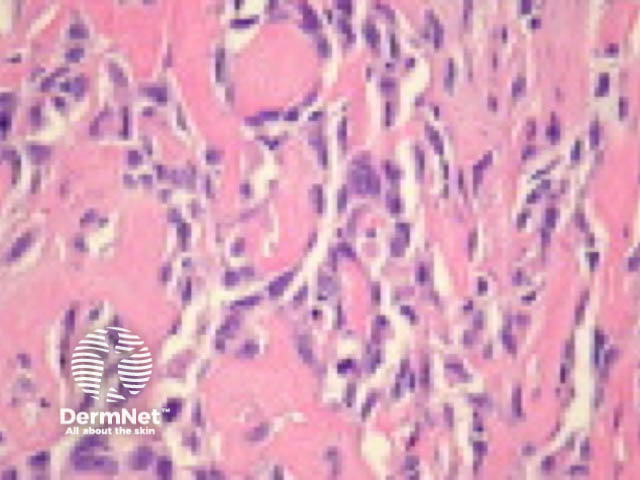

Typical SCC has nests of squamous epithelial cells arising from the epidermis and extending into the dermis (figure 1). The malignant cells are often large with abundant eosinophilic cytoplasm and a large, often vesicular, nucleus. Variable keratinisation (keratin pearls etc) is present (figure 2).

Figure 1